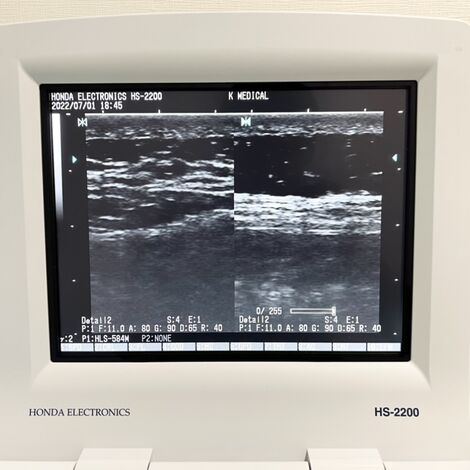

• 必要に応じて超音波エコーで筋肉や靭帯の状態を確認